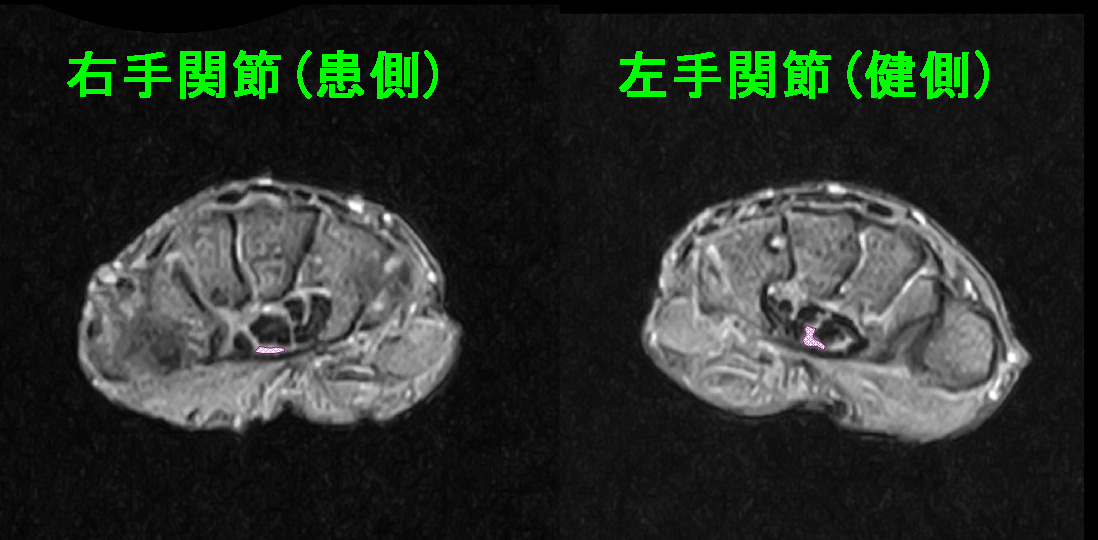

頚椎MRI検査施行。

HWMR.jpg

C2-3中等度~重度の C3-4・C4-5・C5-6・C6-7は中等度の脊柱管狭窄の所見を確認しています。

頚椎に起因する上肢痛・右手のしびれと判断し、当院の頚椎疾患に対する処方を1週行いました。